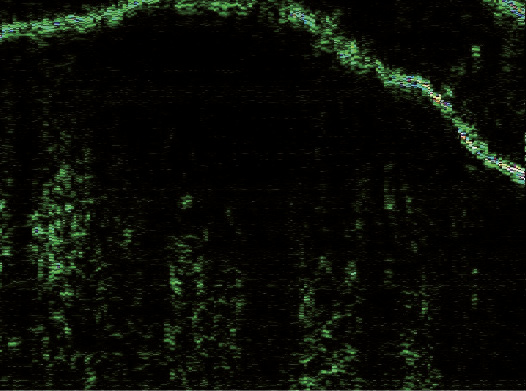

Эпидермис в очагах ББ определялся в виде полосы высокой эхогенности белого цвета с многочисленными желтыми и синими вкраплениями и в виде полосы зеленого оттенка, расположенной под ней. Его внутренний контур был четким и хорошо отграниченным от подлежащей дермы. В зависимости от ультрасонографической картины эпидермиса сканограммы очагов ББ были разделены на две разновидности. В 6 (75%) случаях (1-я разновидность) очаги представляли собой гиперэхогенную полосу неравномерной толщины, волнообразной формы с почкообразными отростками вглубь дермы (рис. 2). В 2 (25%) случаях (2-я разновидность) регистрировали гиперэхогенный слой одинаковой ширины на всем протяжении, с ровным внешним и внутренним контуром (рис. 3).

Рис. 3. Сканограмма болезни Боуэна (датчик 75 МГц). Гиперэхогенный эпидермис одинаковой ширины на всем протяжении, с ровным внешним и внутренним контуром (разновидность 2). Гипоэхогенная зона определяется в виде образования округлой формы с нечеткими границами

Дерма имела четкое отграничение от подкожно-жировой клетчатки и равномерную ширину, В ней определялись гипоэхогенные образования, расположенные непосредственно под эпидермисом, полосовидной или округлой формы, диффузно-неоднородной структуры. Четкие контуры отмечались в 6 случаях (75%) и размытые – в 2 (25%). При этом полосовидная форма встречалась в очагах 1-й разновидности (см. рис. 2), а округлая – 2-й (см. рис. 3). Средние значения толщины эпидермиса, дермы в очагах поражения и коллатеральных участках, а также глубины распространения гипоэхогенных зон приведены в таблице.

При высокочастотном ультразвуковом сканировании отмечалось статистически значимое увеличение средней ширины эпидермиса в очагах ББ по сравнению с контрлатеральными, визуально неизмененными участками кожи (р < 0,05). Визуализировалось две его разновидности – волнообразная с почкообразными отростками вглубь дермы и в виде равномерной полосы, обе имели четкий внутренний контур.